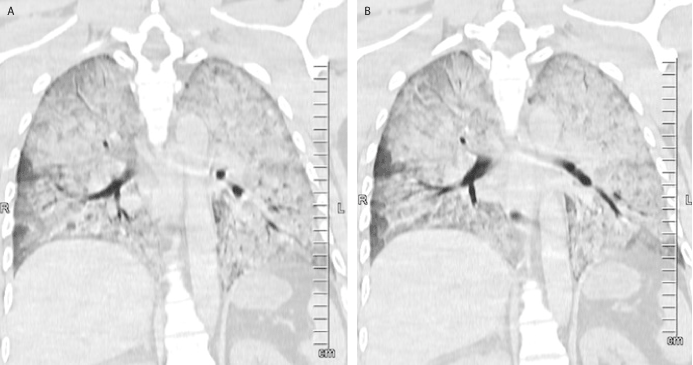

Thoracic CT scans demonstrated the bilaterally diffuse alveolar edema which consistent with neurogenic pulmonary edema (Figure 3 and 4).

Figure 4A and 4B. The coronal section thoracic CT scans showing the bilaterally diffuse alveolar edema(A and B)